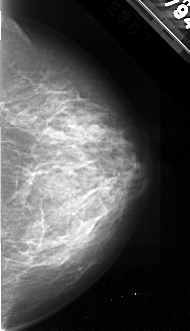

A_1097_1.LEFT_MLO

LEFT_MLO LINES 5506 PIXELS_PER_LINE 2521 BITS_PER_PIXEL 16 RESOLUTION 42 OVERLAY